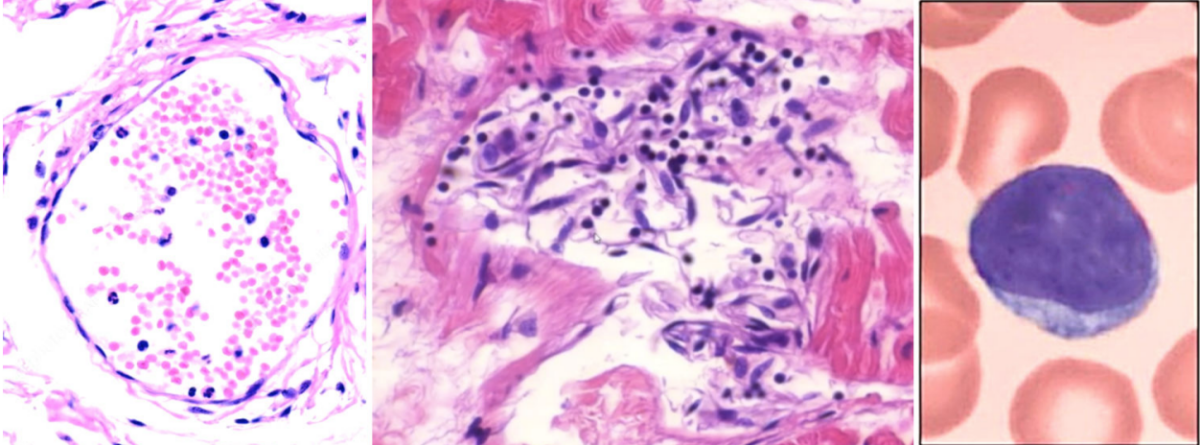

Metodele folosite de dr. Burkhardt se numesc histopatologie și imunohistochimie.

Tehnica este explicată în studiu: „Dacă o particulă de vaccin – compusă din ARNm care codifică Spike, acoperit cu lipide – intră într-o celulă a organismului, aceasta va face ca proteina Spike să fie sintetizată în interiorul celulei și apoi dusă la suprafața celulei. De acolo, poate fi recunoscută de un anticorp specific pentru Spike.”

„După spălarea specimenului de țesut pentru a îndepărta moleculele de anticorpi libere, cele legate pot fi detectate cu un anticorp secundar care este cuplat cu o enzimă, adesea peroxidază [derivată] din hrean. După o altă etapă de spălare, specimenul este acoperit cu un colorant precursor solubil în apă care este transformat de enzimă într-un pigment maro insolubil. Fiecare moleculă de enzimă poate converti rapid un număr mare de molecule de colorant, ceea ce amplifică mult semnalul”, se arată în document.

„În dreapta sus a imaginii, puteți vedea două celule care au fost expuse la vaccinul Pfizer și apoi supuse protocolului prezentat mai sus. Pata maro intensă indică faptul că celulele au produs proteina Spike”, se arată în studiu, referindu-se la imaginea 3.

Inflamația vaselor de sânge

Potrivit lui Lindsay, a doua cea mai mare descoperire este observarea leziunilor endoteliale – inflamație și celule endoteliale denudate în interiorul vaselor de sânge.

Endoteliul este țesutul care căptușește vasele de sânge și alte organe, cum este inima.